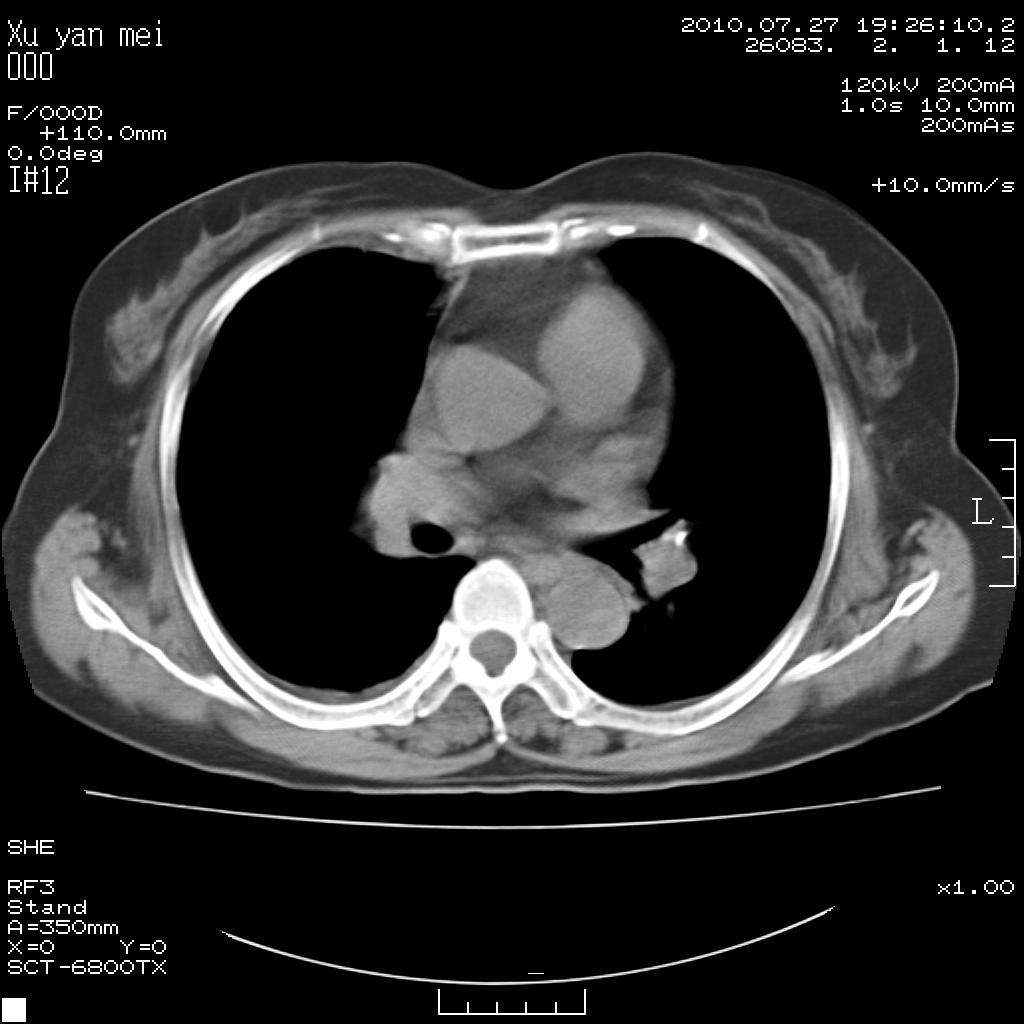

女,60岁,胸痛就诊,右肺结核?炎症?其它?(胸片右侧中上肺野确实看不到什么啊)

1)考虑两肺感染性病变;建议抗炎治疗后复查。2)双侧少量胸腔积液。

1)考虑两肺感染性病变;建议抗炎治疗后复查。2)右侧少量胸腔积液。

双肺炎症可能性大,建议抗炎后复查。右侧胸腔少量积液。双侧胸膜轻度增厚。